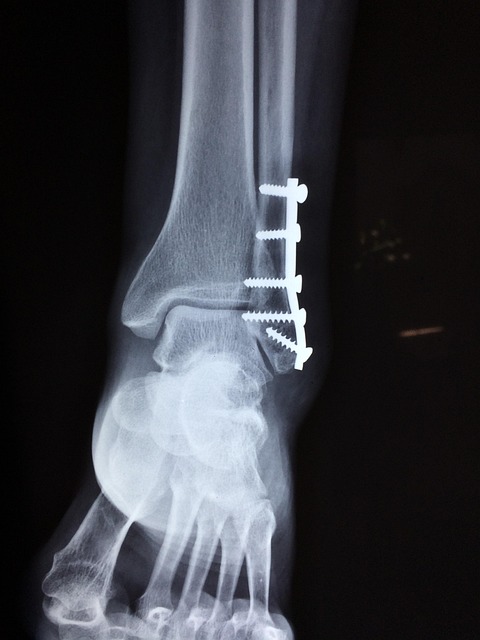

3. 사소한 충격에도 골절

가벼운 넘어짐에도 손목·엉덩이·척추 골절이 발생할 수 있어요.